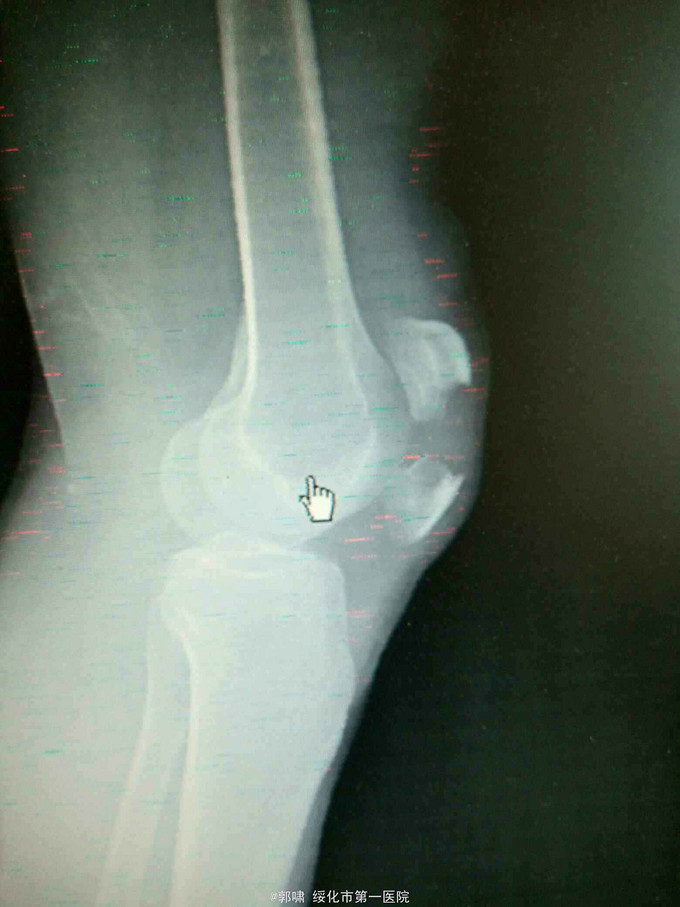

左膝关节摔伤,肿胀,畸形,活动受限一小时。收入院。患者于一小时前滑倒摔伤。当即倒地,左膝关节肿胀,畸形不能行走。门诊拍片示:左膝关节髌骨骨折,断端移位。门诊以左髌骨骨折收入院。

左膝关节肿胀,局部畸形,不能下地行走。浮髌试验阳性。拍片示:左髌骨骨折。

诊断:左髌骨骨折。立即予以腰麻下行切开复位内固定术。术中复位骨折,缝合筋膜,冰水浸泡髌骨爪约10分钟。待髌骨爪变软。选取合适大小的髌骨爪。应用记忆合金髌骨爪内固定。立即用40°温盐水热敷局部。使记忆合金加速抓紧。环抱。缝合爪齿二道,防止脱落。缝合关节囊,韧带组织。术毕。